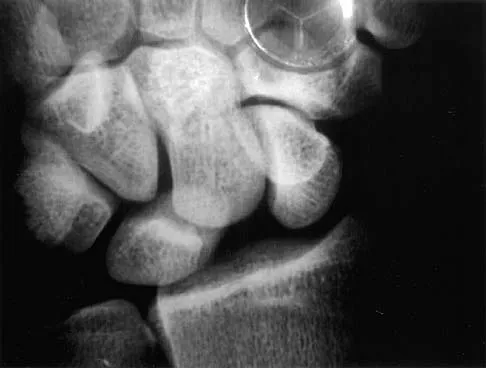

Based on the radiographic findings shown in Figure 41, which of the following wrist ligaments is most likely disrupted?

Explanation